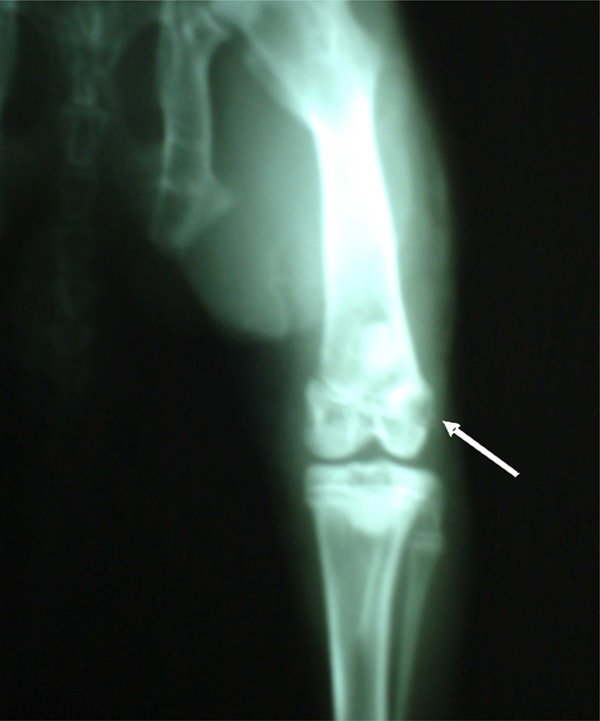

After surgery, radiological studies were immediately carried out on all rabbits, in an attempt to view the lesion and/or the implant at a radiological level (see Fig. 4). As post-surgical control, night and day temperatures studies, as well as hemograms, were performed according to conventional techniques, the grade of food, and the water intake. Tomographic studies, using a Toshiba multislice 16 detectors scanner, were performed at the end of the experiment (45 days).

Radiological studies clearly showing the implanted area.

Image obtained in Multislice CT scanner Toshiba (16 slice) shows a bone lesion in a rabbit femur according to material and method. A radiolucent image with cortical erosion in distal femoral epiphysis of right condyle is observed. Dense image interpreted as signs of incipient integration-regeneration. No swelling of soft tissue is seen.

Once the type of matrix has been selected, the specific lesions and the sample sizes used to test the lesion repair in an in vivo study were defined. The model selected for this study was a femoral bone lesion of three-year old female New Zealand rabbits to consider if the positioning of the mentioned implant did in fact promote the regeneration of de novo bone tissue, and whether or not the rejection phenomena could be discarded. For this, samples of 6 mm in diameter and 3 mm in thickness were cut, sterilized with ethylene oxide, and rehydrated in the blood from each animal, prior to their implants under sterile conditions. According to the proposed technique, a simple and practical lesion was obtained with clear edges. Post-surgical radiological studies, performed in the rabbits that received the implant, clearly showed the opaque area of the implant (Fig. 4).

After 45 days, tomographic studies (Toshiba multislice scanner) showed, in all animals from the Imp group, punched out implanted areas of clean rim in the non-articular femoral direction, dense images compatible with incipient integration, minimum signs of phlogosis, and no signs of rejection at the imaging level (Fig. 5). By contrast, the noI group presented typical unclean rim lesions in all cases (due to an incipient fibrosis process which is typical in lesions that cannot be resolved through therapeutic strategies, in turn generating fibrous tissue that do not have the characteristics of the original tissue prior to the incision).